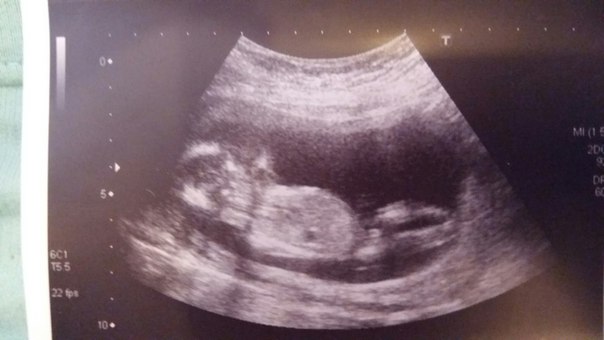

15-я неделька. Мы узнали пол! Фото)))

УЗИ, КТГ, доплерДевочки, всем привет! Вернулись с УЗИ. И у нас будет...

СЫН! Сыночек! Наш мальчишка))) Так не привычны для меня эти слова! И вообще, что делать с мальчиками????АААА!!!)))) В общем я рада! И муж конечно же счастлив! На УЗИ все показали-увеличили. Врач сказала, что ничего не отвалится уже 100%. Вот такие вот дела!

Сегодня у нас по мес. 14.6, по УЗИ 14.3. Но овуляция поздняя была, если по ней считать, то 13.6.

Девочки, посмотрите, пожалуйста, это ж мальчик?